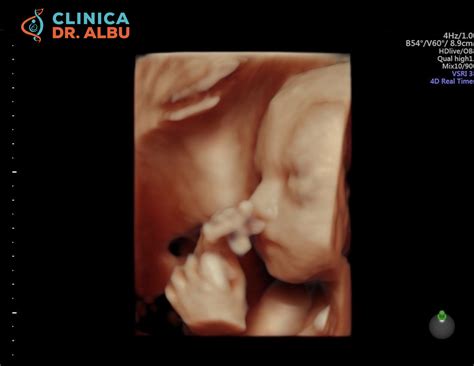

Ecografia morfologică de trimestrul II

Ecografia morfologică de trimestru doi de sarcină este o ecografie foarte detaliată a bebelușului. Se efectuează, de regulă, în săptămâna 21 sau 22 de sarcină, de către un medic cu supraspecializare pe medicină materno-fetală sau de către un medic cu experiență în morfologie fetală. Această ecografie analizează în detaliu bebelușul pentru a afla dacă există semne ale unor anomalii sau malformații.

Săptămânile 19 - 23

Atunci când dezvoltarea fetală se consideră încheiată, ecografia apreciază morfologia fetală în detaliu, stabilește cu acuratețe localizarea placentară și reevaluează caracteristicile circulatorii prin interogare Doppler. Măsurarea colului uterin se va face corect prin examinare transvaginală. Ca metodă suplimentară de diagnostic prenatal, în prezența unor anomalii fetale, examinarea ecografică poate fi completată cu examinarea prin RMN.